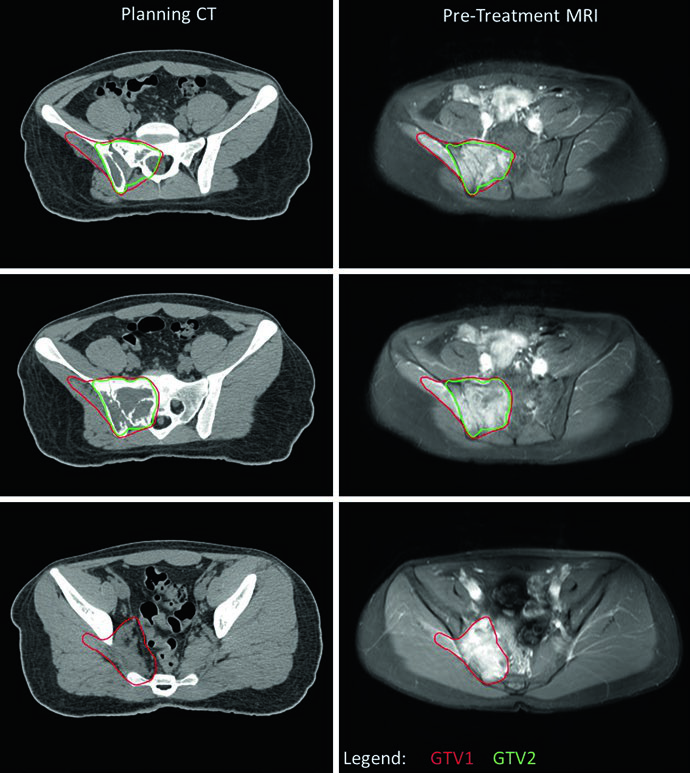

O planejamento no EWS utiliza dois conjuntos de volumes: um baseado na extensão da doença ao diagnóstico (GTV1/CTV1) e outro definido pela doença residual pós-quimioterapia e, eventualmente, pós-cirurgia (GTV2/CTV2). As margens adicionadas aos CTVs para incerteza de posicionamento resultam nos respectivos PTVs.

| GTV1 | Extensão pré-quimioterapia da doença macroscópica (osso e partes moles), incluindo linfonodos suspeitos não ressecados. O GTV1 pode ser modificado se o tumor inicial se estendia para cavidades corporais (pelve, tórax) e houve regressão com quimioterapia. |

| GTV2 | Tumor residual após quimioterapia de indução; contudo, toda extensão óssea pré-quimioterapia é tipicamente incluída no GTV2. No pós-operatório, o GTV2 corresponde à doença residual (óssea ou de partes moles) e sítios de margens positivas. |

Um ponto prático central é o manejo do GTV1 quando o tumor se estende para cavidades corporais. Se a imagem pré-tratamento mostra tumor “empurrando” pulmão ou vísceras pélvicas — sem invasão direta — o GTV1 pode ser adaptado após a quimioterapia de indução para refletir a regressão tumoral nesses espaços. Essa adaptação aparece claramente no caso de EWS pélvico, onde o nível inferior não apresenta doença residual (GTV2) e a extensão do GTV1 para a pelve foi reduzida para compensar a resposta à quimioterapia. O PTV1 recebeu 45 Gy e o PTV2 recebeu 10,8 Gy adicionais, totalizando 55,8 Gy.